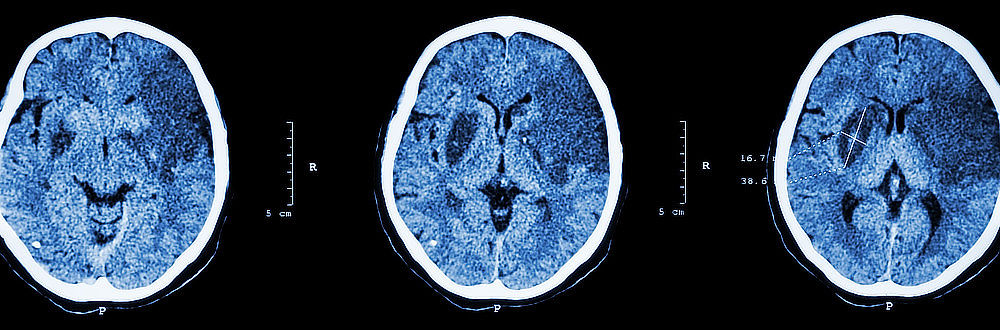

CT – hlavní diagnostická metoda

Prvním vyšetřením u pacienta s podezřením na cévní mozkovou příhodu je vždy výpočetní tomografie (CT). Pomocí CT lze s velmi vysokou mírou jistoty prokázat či vyvrátit přítomnost krvácení do mozku. Při tomto vyšetření je pacientova hlava rentgenována z různých úhlů, což umožňuje mnohem lepší a komplexnější zobrazení vyšetřované tkáně než prostý rentgenový snímek. Obrázky řezu poskytují informace o umístění, rozsahu a příčině oběhové poruchy. CT vyšetření je bezbolestné.